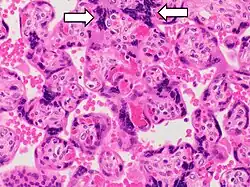

Histopathology of placenta with increased syncytial knotting of chorionic villi, with two knots pointed out.